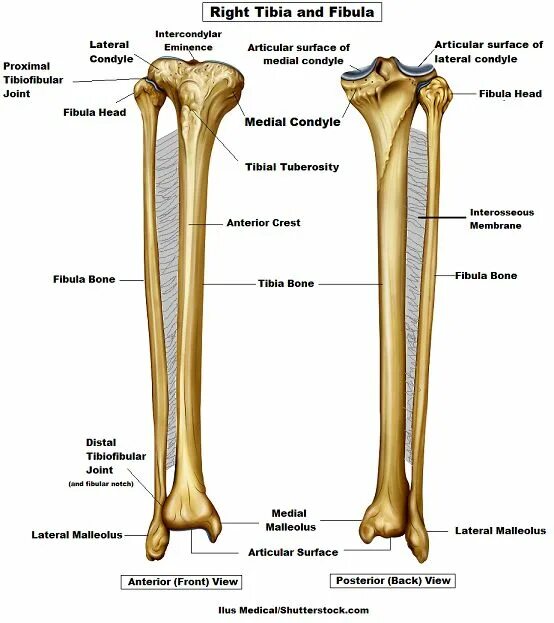

Curved tibia fibula